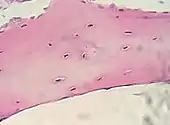

Bone, cell nuclei (blue-purple), bone matrix (pink).

Lung tissue taken from an emphysema patient. Cell nuclei (blue-purple), red blood cells (bright red), other cell bodies and extracellular material (pink), and air spaces (white). Muscle tissue, cell nuclei (blue-purple), cell body (pink).

Muscle tissue, cell nuclei (blue-purple), cell body (pink)..jpg.webp) Basal cell carcinoma of the skin, cell nuclei (blue-purple), extracellular material (pink).